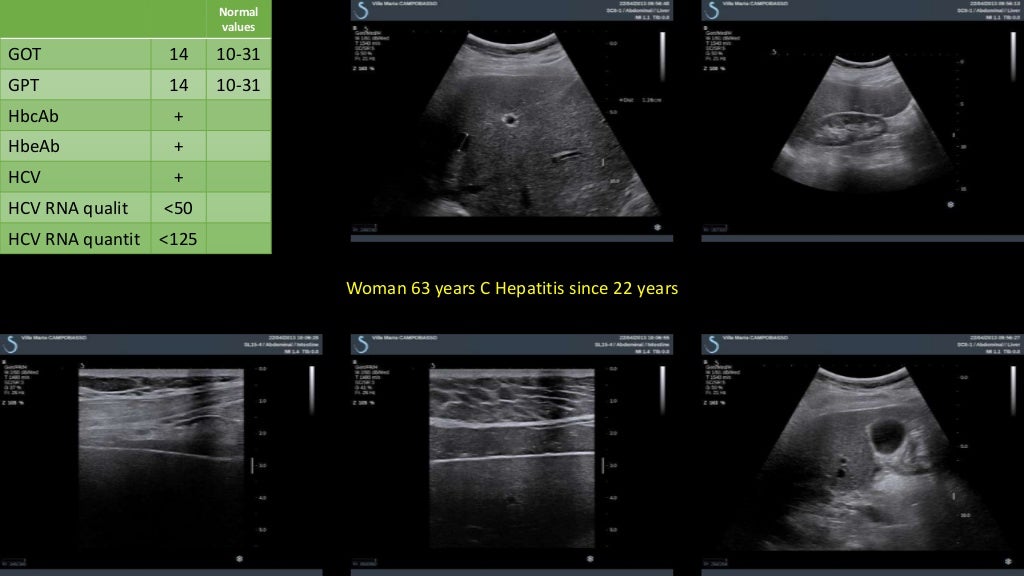

Dr. masciotra liver shear wave elastography clinical cases

Dr. masciotra liver shear wave elastography clinical cases What Is Normal Liver Shear Wave Speed A significant correlation was found between age and shear wave velocity (swv) value. In stiffer tissue they propagate faster [2, 3]. Physical principles of shear wave elastography. the hvpg is the difference between the free hepatic venous pressure (a measurement of systemic blood pressure) and the wedged/occluded. shear wave elastography encompasses several different methods of measuring shear wave. What Is Normal Liver Shear Wave Speed.